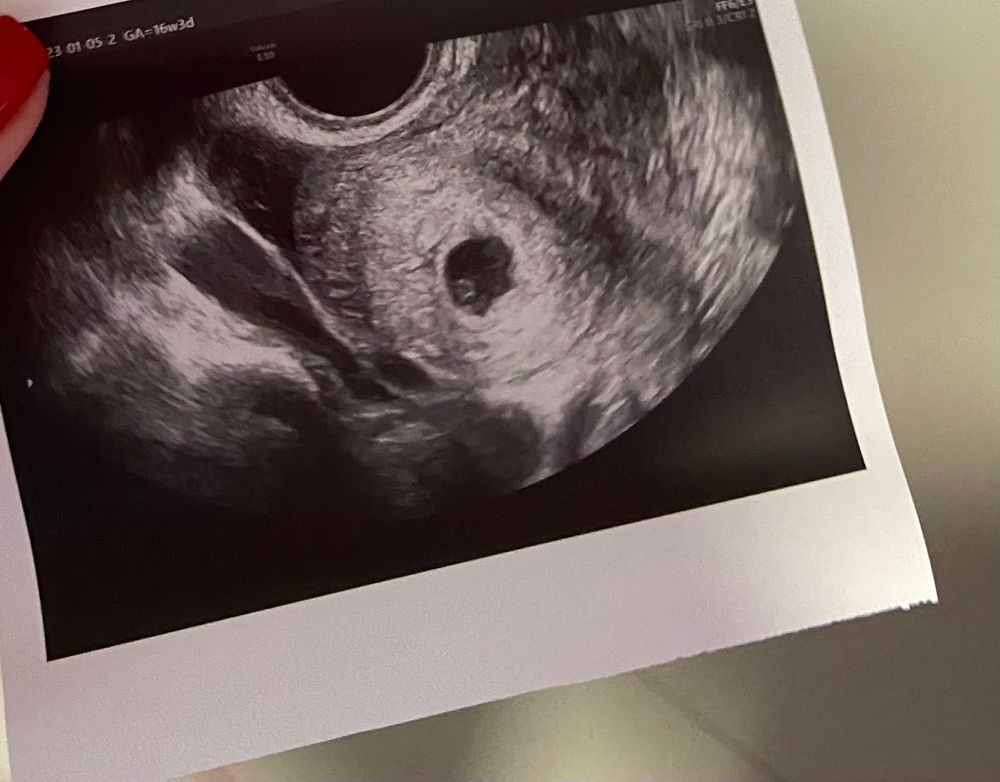

Официально беременна-первое УЗИ

Официально врываюсь в 1 триместр.Первое узи и привет малыш👋расти дальше

по М срок 5+5

Мария, там много вопросов,но,к сожалению,я знаю так мало ответов.пока увидели только ПЯ

на счет эмбриона и сб думаю еще рано,раз об этом не говорили мы

знаю.что все хорошо

дальше через 2 недели